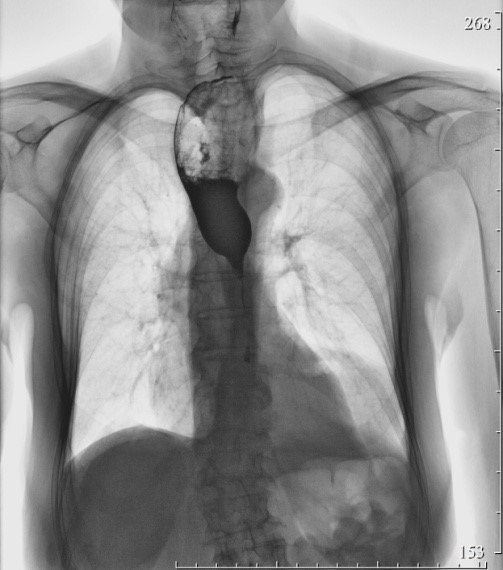

2185. Из анамнеза известно, что в течение длительного времени пациент страдает тяжелым рефлюкс-эзофагитом, осложнившимся развитием